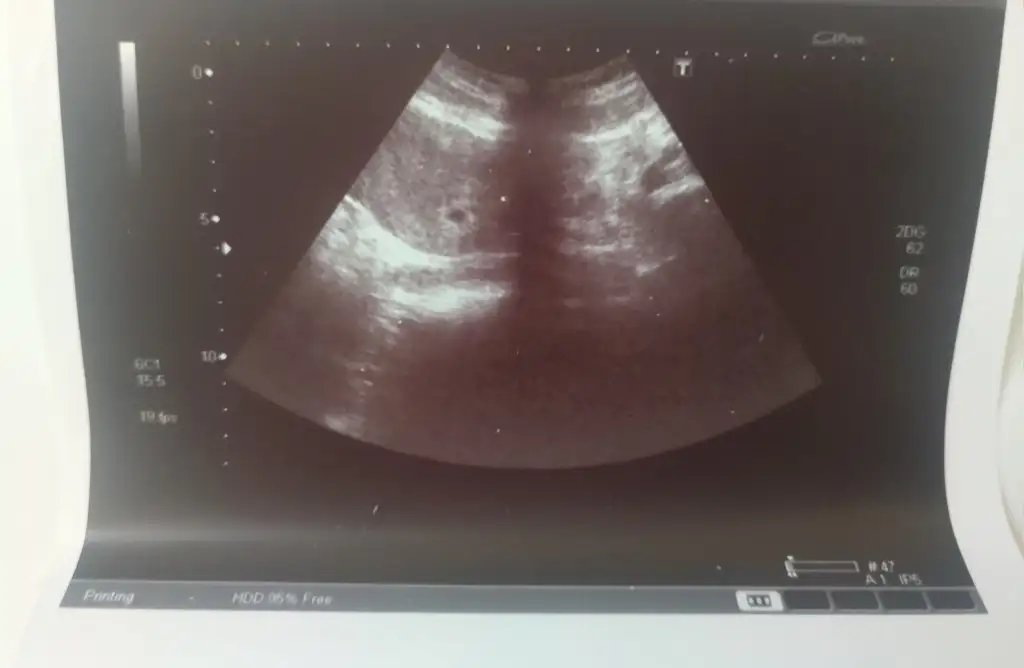

Merhaba kizlar bugun bizde gittik kontrole vajinal ultrasondan gozuktu benim hesabima gore son adet gunum 7 nisandi 6 hafta gibi cikiyordu ama 4+4 olarak cikti cunku gec dollenme olmus zaten adet gecikmemin 7 gununde betam 125 cikmisti. Hersey normal dendi rahimde cok guzel tutunmus dedi 6mm gozukuyor resmi sizede birakayim 🥰